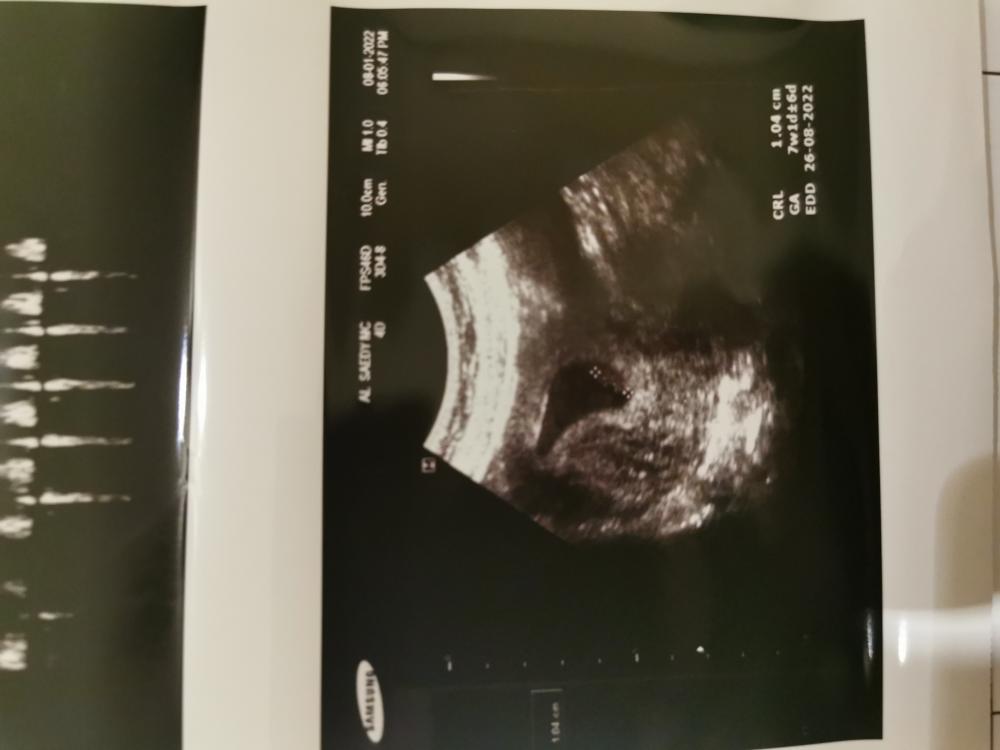

هذا الأسبوع السابع

السلام عليكم ي كروشات كيف حالكم ؟ رحت سويت السونار الييوم ولله الحمد قالولي . . . . . . . . بنووتتته 😍💗💗💗 يلا ياقلبي تواقه لونيني ويعطيك الف عافيه 😘 💗💗💗